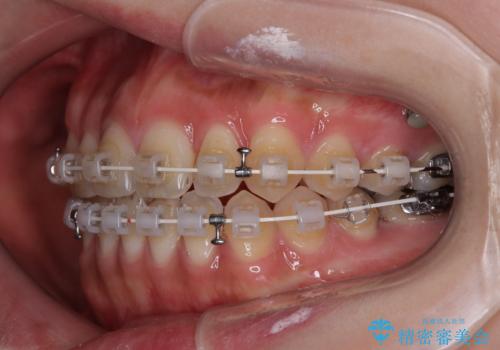

開咬をワイヤー装置で矯正治療

- 上下前歯が非接触となっている咬み合わせを気にして来院された患者様です。

開咬となっている原因の大半は、舌の突出癖によるものであるため、治療開始前から舌のトレーニングを開始し、スムーズに治療が進むようにしました。

開咬の方は、インビザライン矯正治療が適していますが、自己管理の煩わしさと、転勤の可能性がありマウスピース矯正であると通院しなくなるだろうとのことで、ワイヤー装置にて矯正治療を行うこととしました。